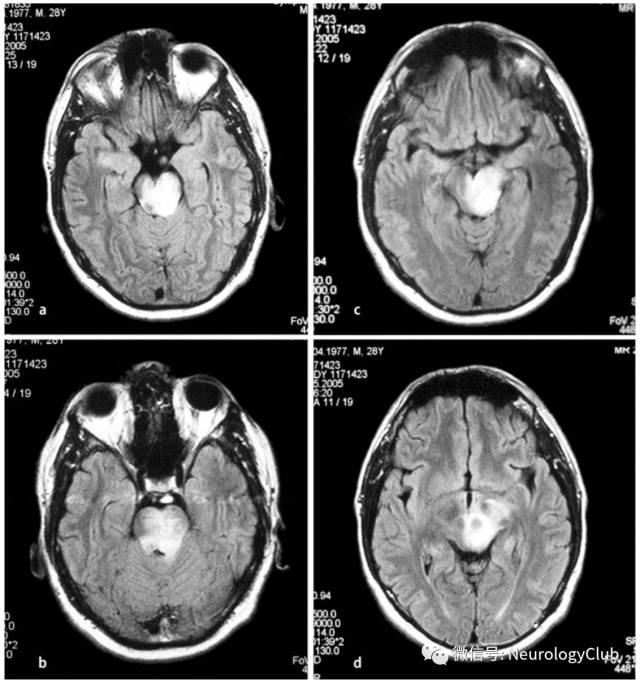

神经白塞病包括实质型和非实质型。实质型神经白塞病约占70-80%,病灶以脑干(脑桥、中脑)常见,也可延伸累及间脑、基底节区。累及大脑半球时,常为多发的小白质病变,也可表现为孤立性类瘤样病灶。脊髓受累时可见单发或多发的不同长度的炎性病变,常位于颈胸髓。也可有脑膜脑炎,表现为脑膜强化。急性期病灶在T1WI上呈等-低信号,增强通常为片状强化,也可出现环形强化,T2WI和FLAIR上为高信号,DWI上高信号,相应ADC值降低。部分病灶中心或周围可见出血。累及脊髓时横断面T2WI可见“百吉饼(在美国纽约较为流行,也称硬面包圈)征(Bagel Sign)”。慢性期,病灶多缩小,通常无强化,可见脑萎缩,尤其是脑干。

(图4:FLAIR可见脑桥与中脑受累,延伸累及间脑)

(图5:T2WI可见中脑病灶,延伸累及间脑和基底节区